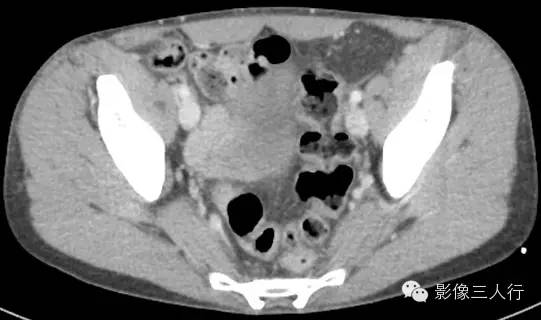

延盲肠层面向下延续能看到腹股沟管走行区可见到管状的阑尾影像,腔内可见气体密度,阑尾壁无增粗,周围无明显渗出。